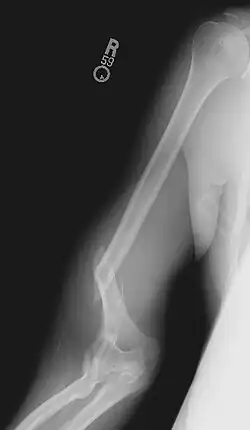

Травматизм

Кажущаяся простота движений создаёт у многих иллюзию доступности вида спорта. Вид спорта травмоопасен: нагрузки на локтевые и плечевые суставы, связки, кости предплечья и плеча очень велики. Для избежания подобных травм, принципиально употребление кальция для укрепления базы (костей), практика (искусственный оппонент на основе тренажёров) и общее укрепление, упираясь на укрепление жил/сухожилий для предотвращения разрывов мышц.